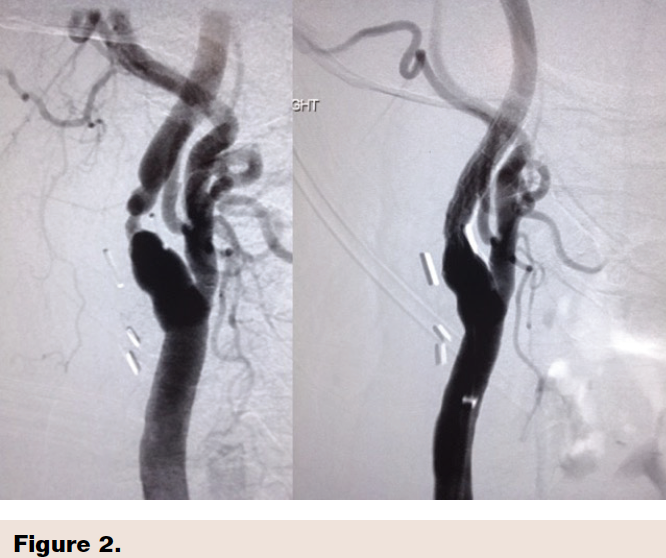

Case example with before and after CAS using the Gore Carotid stent showing excellent clinical result.(Figure 2)